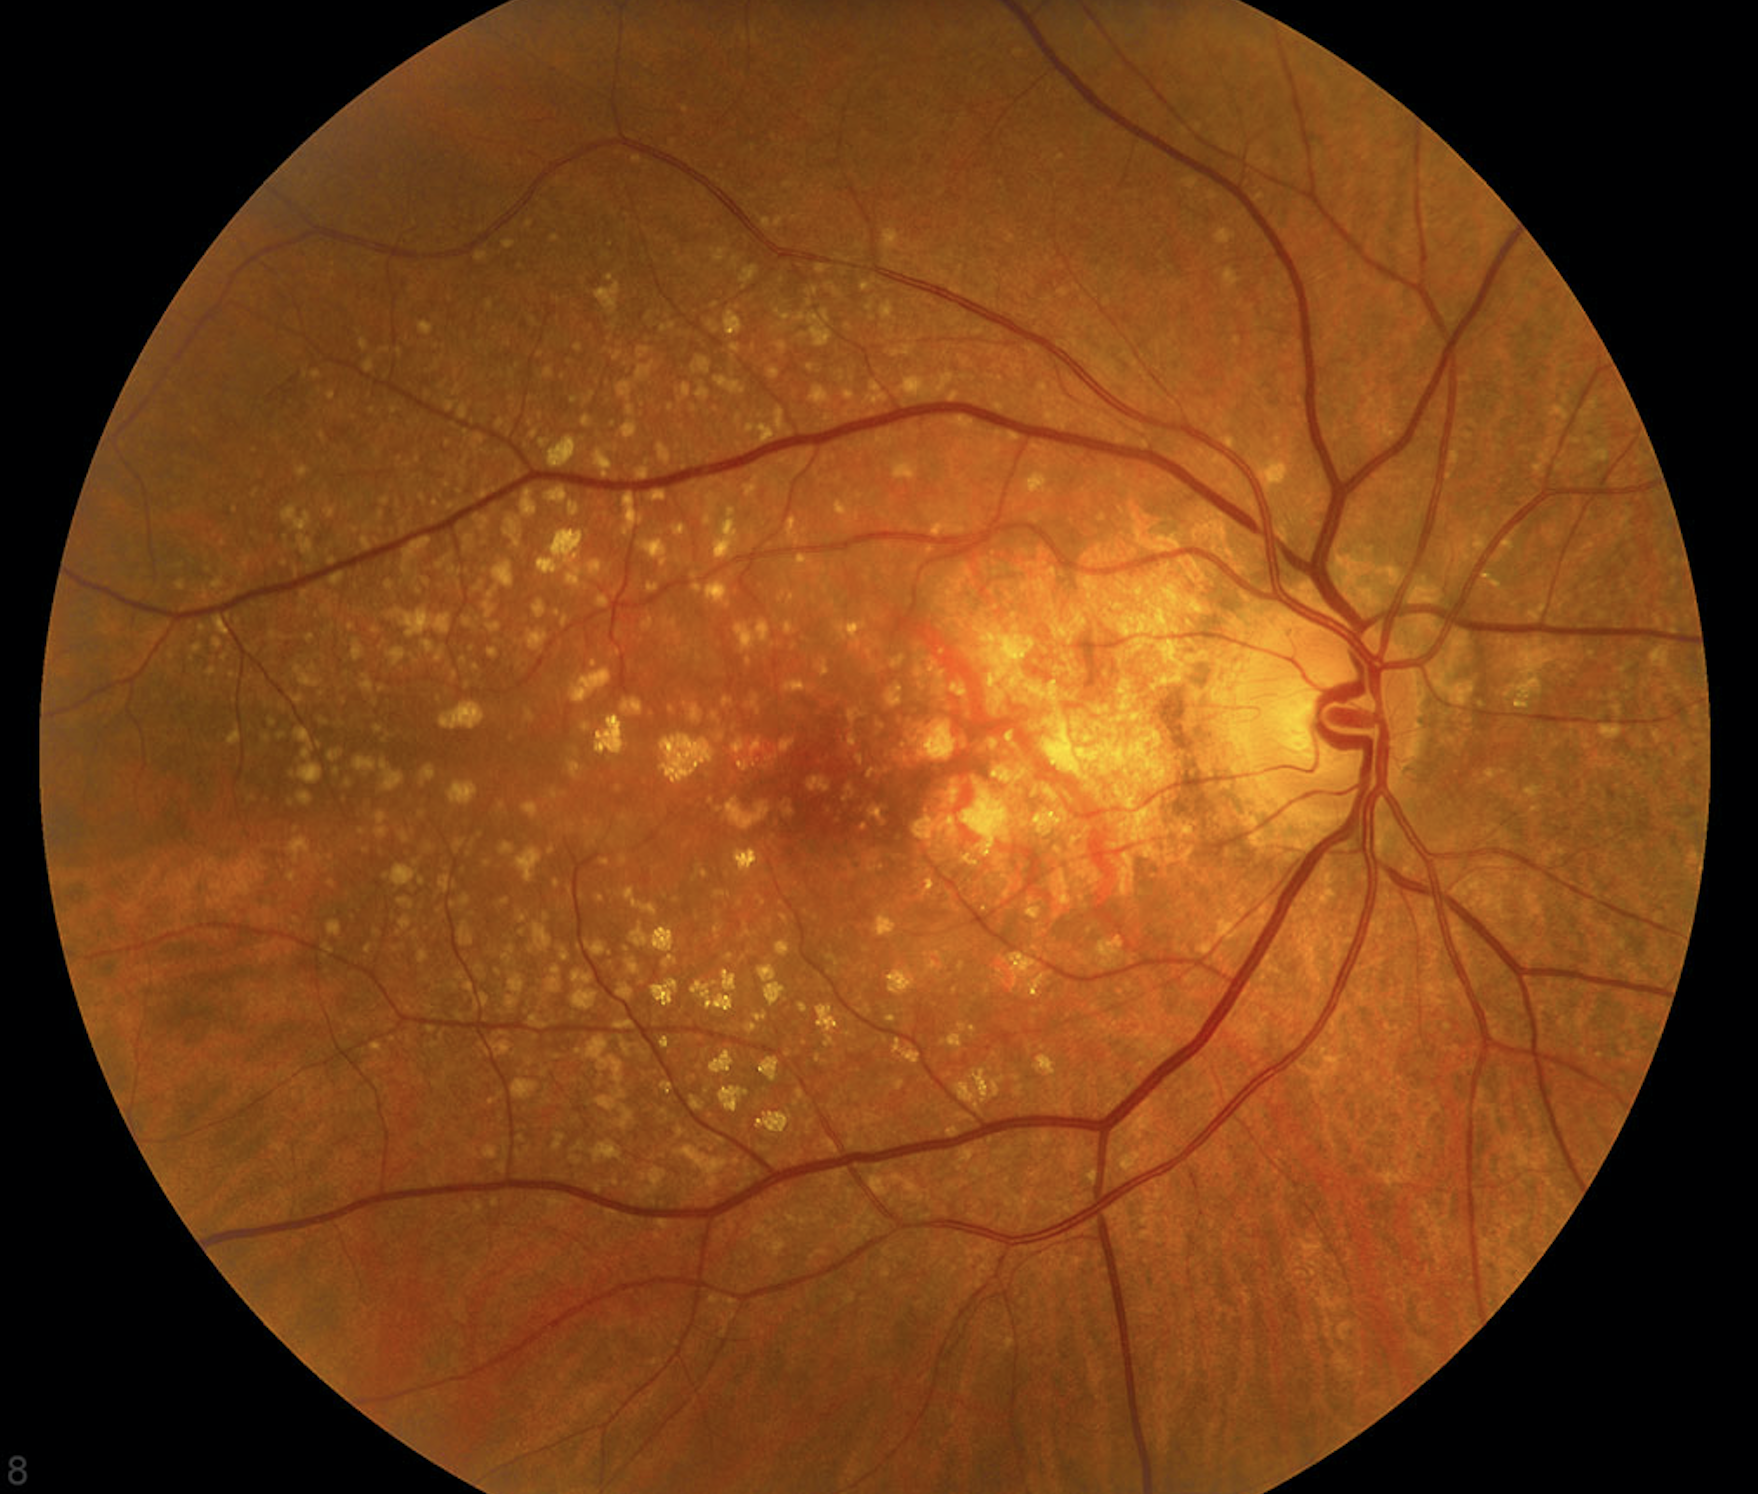

DMRE húmeda

Este tipo es menos común pero mucho más grave. La DMRE húmeda se produce cuando crecen vasos sanguíneos anormales bajo la retina. Estos vasos pueden permear sangre u otros fluidos, lo que provoca cicatrices en la mácula. La visión se pierde más rápido con DMRE húmeda que con DMRE seca.

Muchas personas no notan que tienen DMRE hasta que su visión se ha vuelto muy borrosa. Es por esto que es tan importante visitar a un oftalmólogo con regularidad. El oftalmólogo o la oftalmóloga puede buscar indicios tempranos de DMRE antes de que tenga problemas de visión. (academia americana de oftalmología)